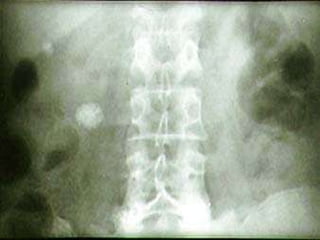

PERCUTANEOUS RENAL SURGERY   PRE – OP WORK UP   Urine culture Renal function test Haematological profile Caogulation profile KUB and IVU US .

X-ray Ultrasonography Which one is better ? 2 methods combination better.why?

X-ray Ultrasonography Whichone is better ? 2 methods combination better.why?